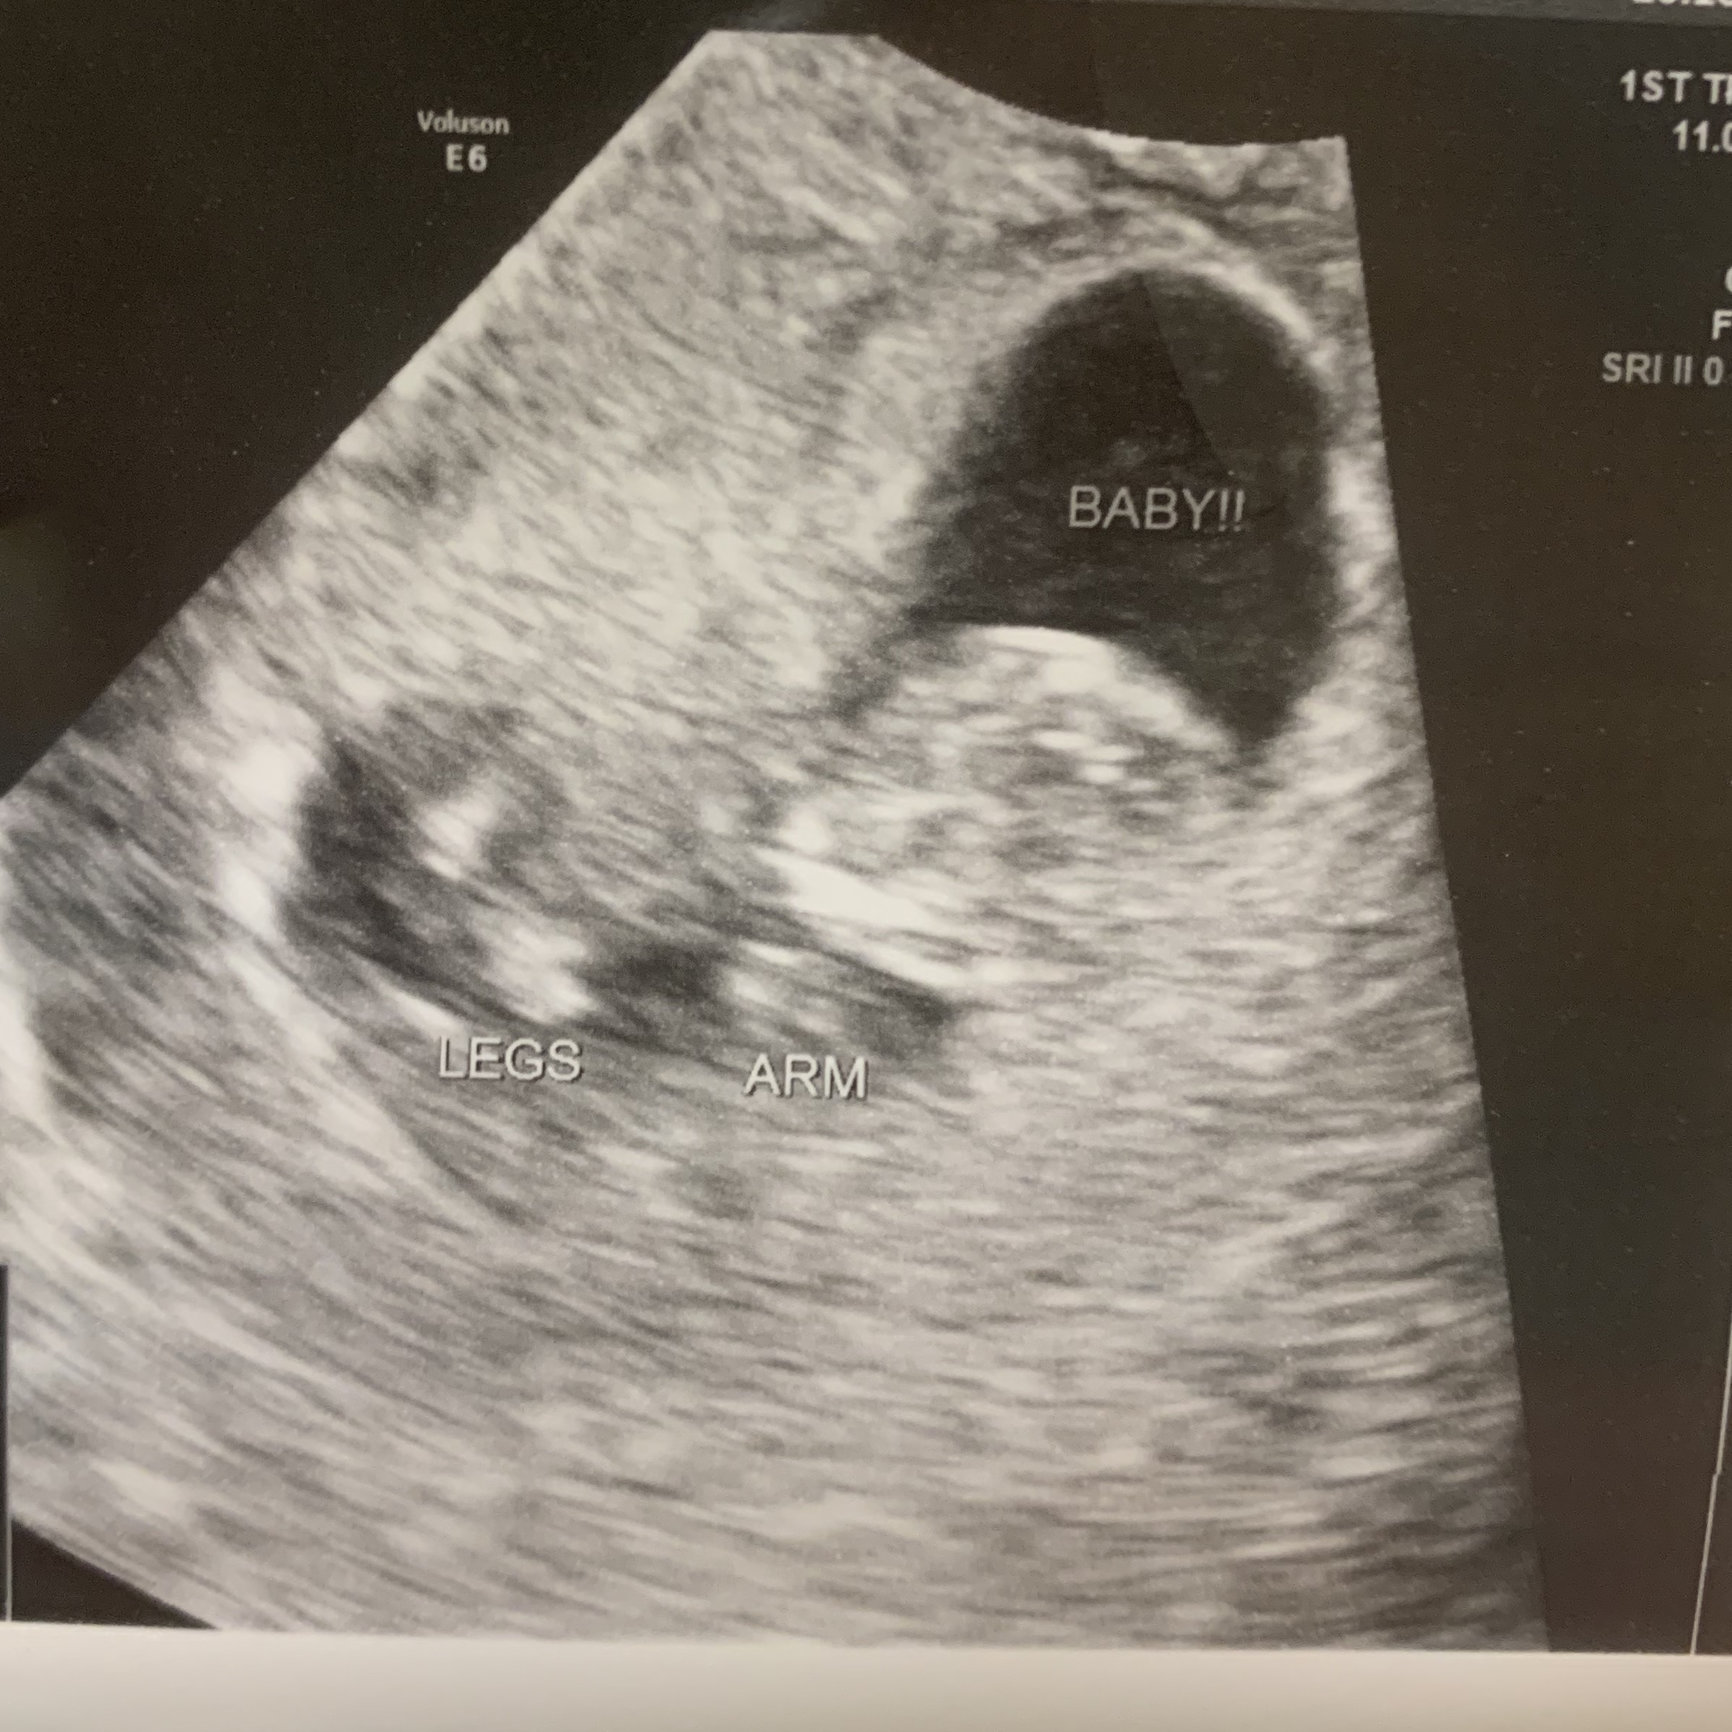

Hi everyone! My EDD is 7/1/2019, so I’m not sure if I’ll be here or in June. Here is our ultrasound photo from 8 weeks (transvaginal) a couple weeks ago. Heartbeat was 172bpm. Baby is the blob on the upper right, facing away.

Here is our ultrasound photo from 8 weeks (transvaginal) a couple weeks ago. Heartbeat was 172bpm. Baby is the blob on the upper right, facing away.